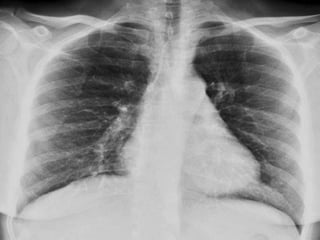

CRITERIOS DE EVALUACIONRX. TX.  Pulmones desde ápex hasta senos costo diafragmáticos  Pulmones y corazón sin rotación.  10 pares de costillas.  Sombra área de la tráquea centrada sobre la columna.  Balance en los contrastes de la imagen (exposición adecuada).

INTERPRETACION  Revisar estructuras óseas.  Partes blandas.  Espacios intercostales.  Parénquima pulmonar  Nivel de los senos costodiafragmaticos.  Neumatización.  Trama alveolo-pulmonar  Silueta cardiaca  Cayado aórtico.